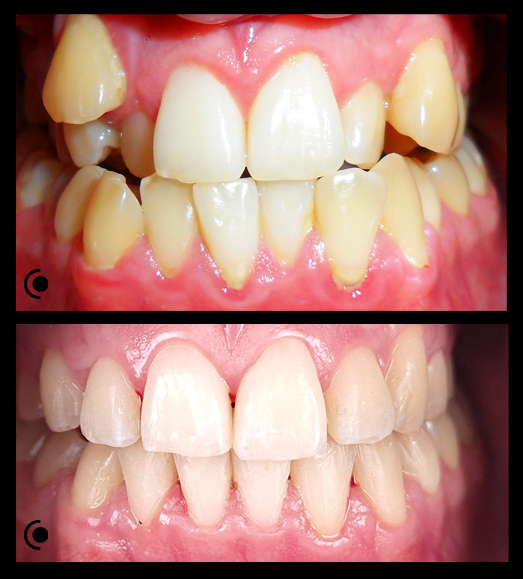

O našoj kvaliteti najbolje govore naši rezultati!

Centar za ortodonciju Petra Džapo